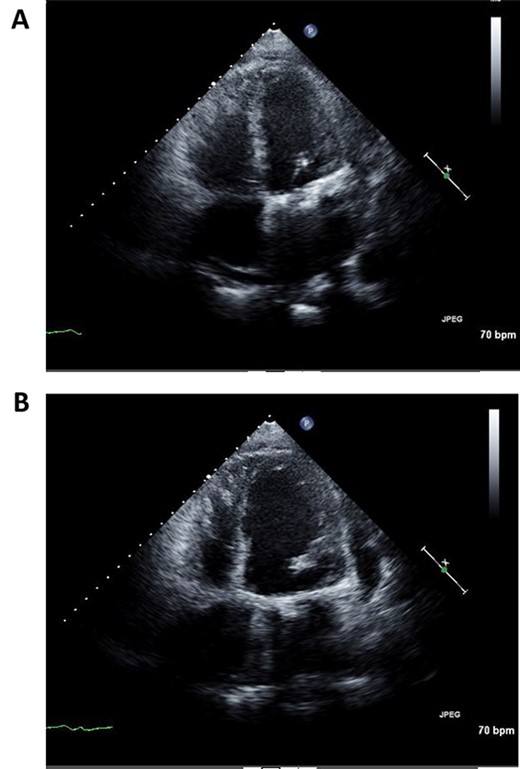

Immediately after the operation, echocardiography revealed improved cardiac function: left ventricular ejection fraction of 37% (Fig. 3A and B). Postoperative course was uneventful and the patient was discharged 2 weeks post operation. Fourth year follow-up revealed further improvement in cardiac function; left ventricular ejection fraction of 42%. The patient continues to do well with NYHA class I status.

Postoperative echocardiography of left ventricle in systolic (A) and diastolic (B) phases.